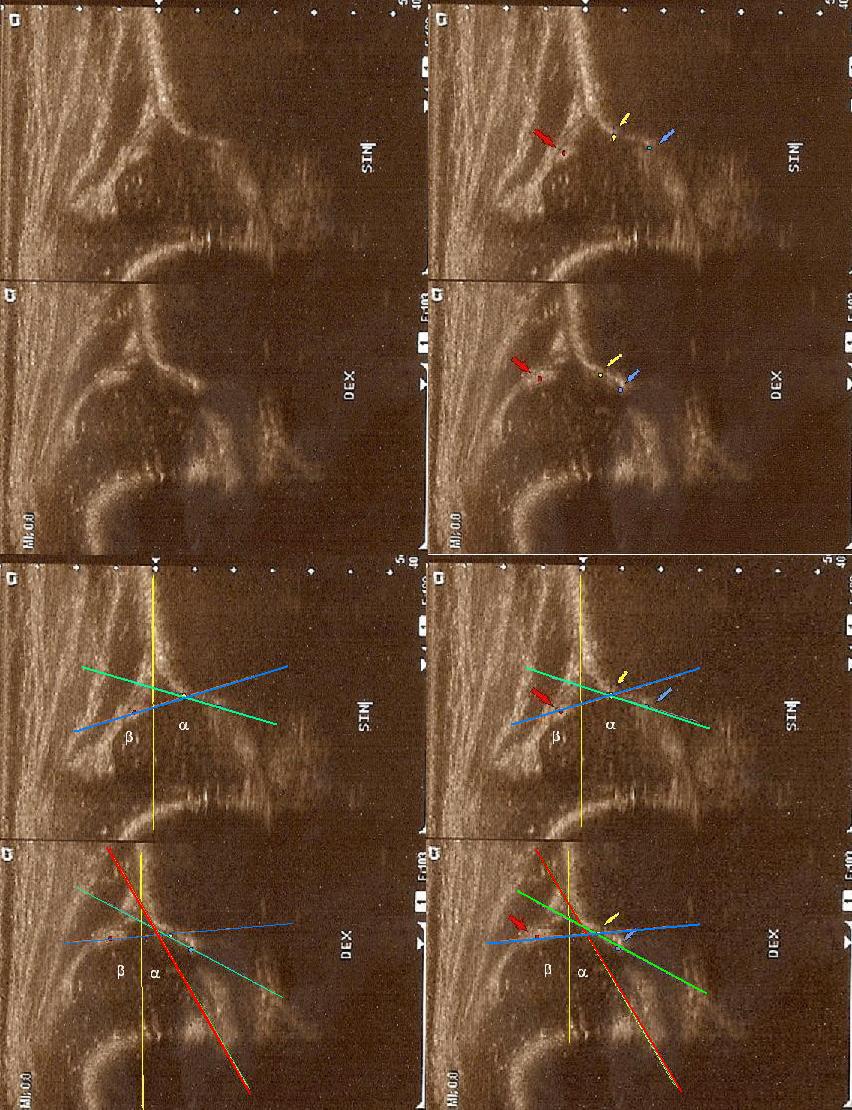

typIIa 4yg.ż.poniżej dach kostny wystarczajacy;brzeg kostny okragły;dach chrzestny pokrywa

górne zdjęcia

strzałki pokazują obrabek(czerwona):brzeg kostny (żółta);gałąż dolna(niebieska) ,

prawidłowy przebieg linii dachu kostnego(niebieska) stycznie do echa gałęzie dolnej i echa brzegu kostnego ;

linii dachu chrzęstnego (czerwona) stycznie do brzegu kostnego i przez środek geometryczny obrąbka i

linii podstawnej ( żółta

)równolegle do sylwetki kości biodrowej po zewnetrznej stronie prze punkt gdzie ochrzęstne przechodzi w okostna i styka sie z echem kości

typ D powyżej 4tyg.ż. dach kostny bardzo niewystarczajacy;brzeg kostny spłaszczony ;dach chrzestny przesunięty dogłowowow ( szczyt głowy jest poniżej szczytu dachu chrzęśtnego)

dolne zdjęcia strzałki pokazują obrabek(czerwona):brzeg kostny (żółta);gałąż dolna(niebieska) ,

prawidłowy przebieg linii dachu kostnego(zielona) stycznie do echa gałęzie dolnej i echa brzegu kostnego ;

linii dachu chrzęstnego (niebieska) stycznie do brzegu kostnego i przez środek geometryczny obrąbka i

linii podstawnej ( żółta)równolegle do sylwetki kości biodrowej po zewnetrznej stronie prze punkt gdzie ochrzęstne przechodzi w okostna

i styka sie z echem kości : w przypadku wysuwania głowy z panewki nie zawsze jest to już pozycja standardowa; sylwetka kosći biodrowej

pochyla sie i powiniśmy kreślic linie zgodnie z odchyleniem w lewo druga czerwona liinia kropkowana ( trzeba o tym pamiętac bo z D

wykreślimy I prawidłowy kąt @ o wartości 62 st jest to najczęstszy błąd; u kikutygodniowych niemowląt kiedy zmiany wtórne

nie sa jeszcze wykształcone; o poważnych konsekwencjach zwłaszcza jeśli korzystamy z programów do automatycznego wykreslania kątów )

typ IIc powyzej

6tyg.ż. dach kostny bardzo niewystarczajacy;brzeg kostny spłaszczony

;dach chrzestny jeszcze pokrywa ( obraz przypomina odwrócone V)

dolne zdjęcia

strzałki pokazują obrabek stawowy(czerwona):brzeg kostny (żółta);gałąż dolna(niebieska) ,

równolegle do sylwetki kości biodrowej po zewnetrznej stronie prze punkt gdzie ochrzęstne przechodzi w okostna i styka sie z echem kości